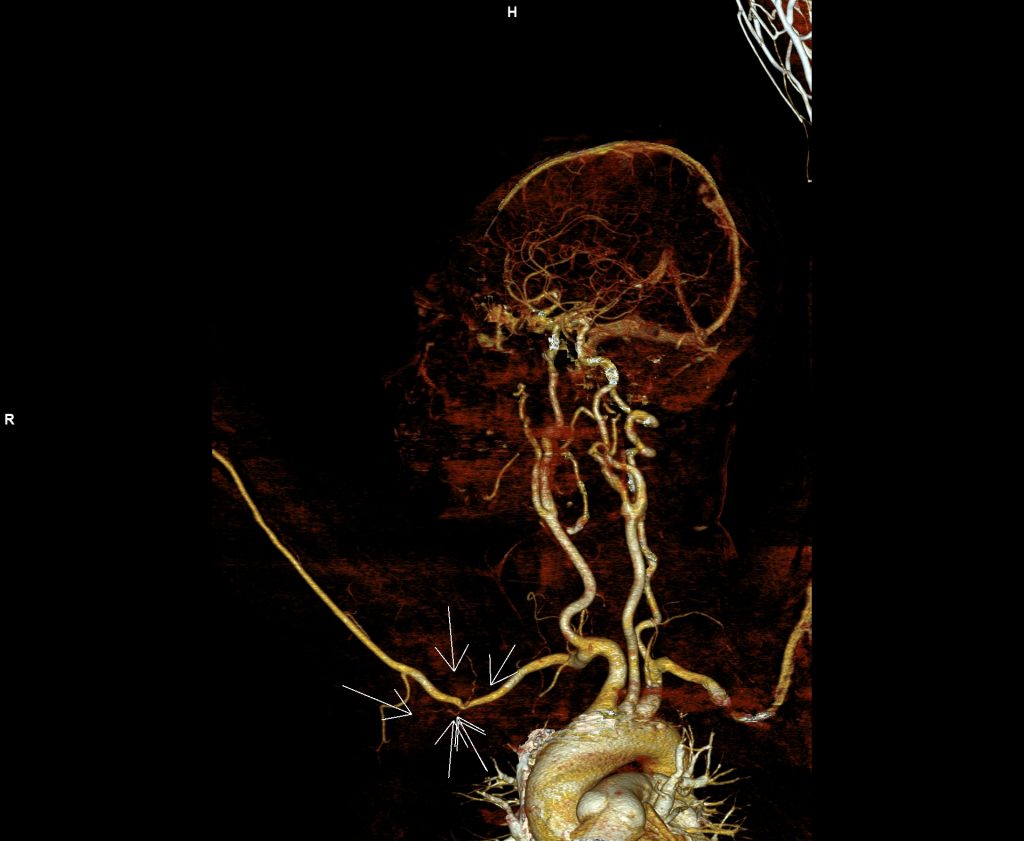

Figura 2: reconstrucție în axul vasului MIP (maximum intensity projection) din achiziție în timp arterial cu evidențierea modificării de calibru a arterei axilare

Discuţie caz nr 40: pacienta cunoscută cu neoplasm mamar este trimisă la examinare angioCT pentru suspiciune ecografică de tromboză de venă axilară dreapta. Se evidențiază o leziune expansivă densă cu priză de contrast în timp venos situată în vârful axilei drept care invadează pachetul vascular axilar determinând reducere de calibru a arterei axilare drepte și ocluzia venei axilare drepte cu dezvoltare de circulație colaterală de tip venos  la nivelul țesutului subcutanat al hemitoracelui drept și în musculatura paravertebrala posterioară.